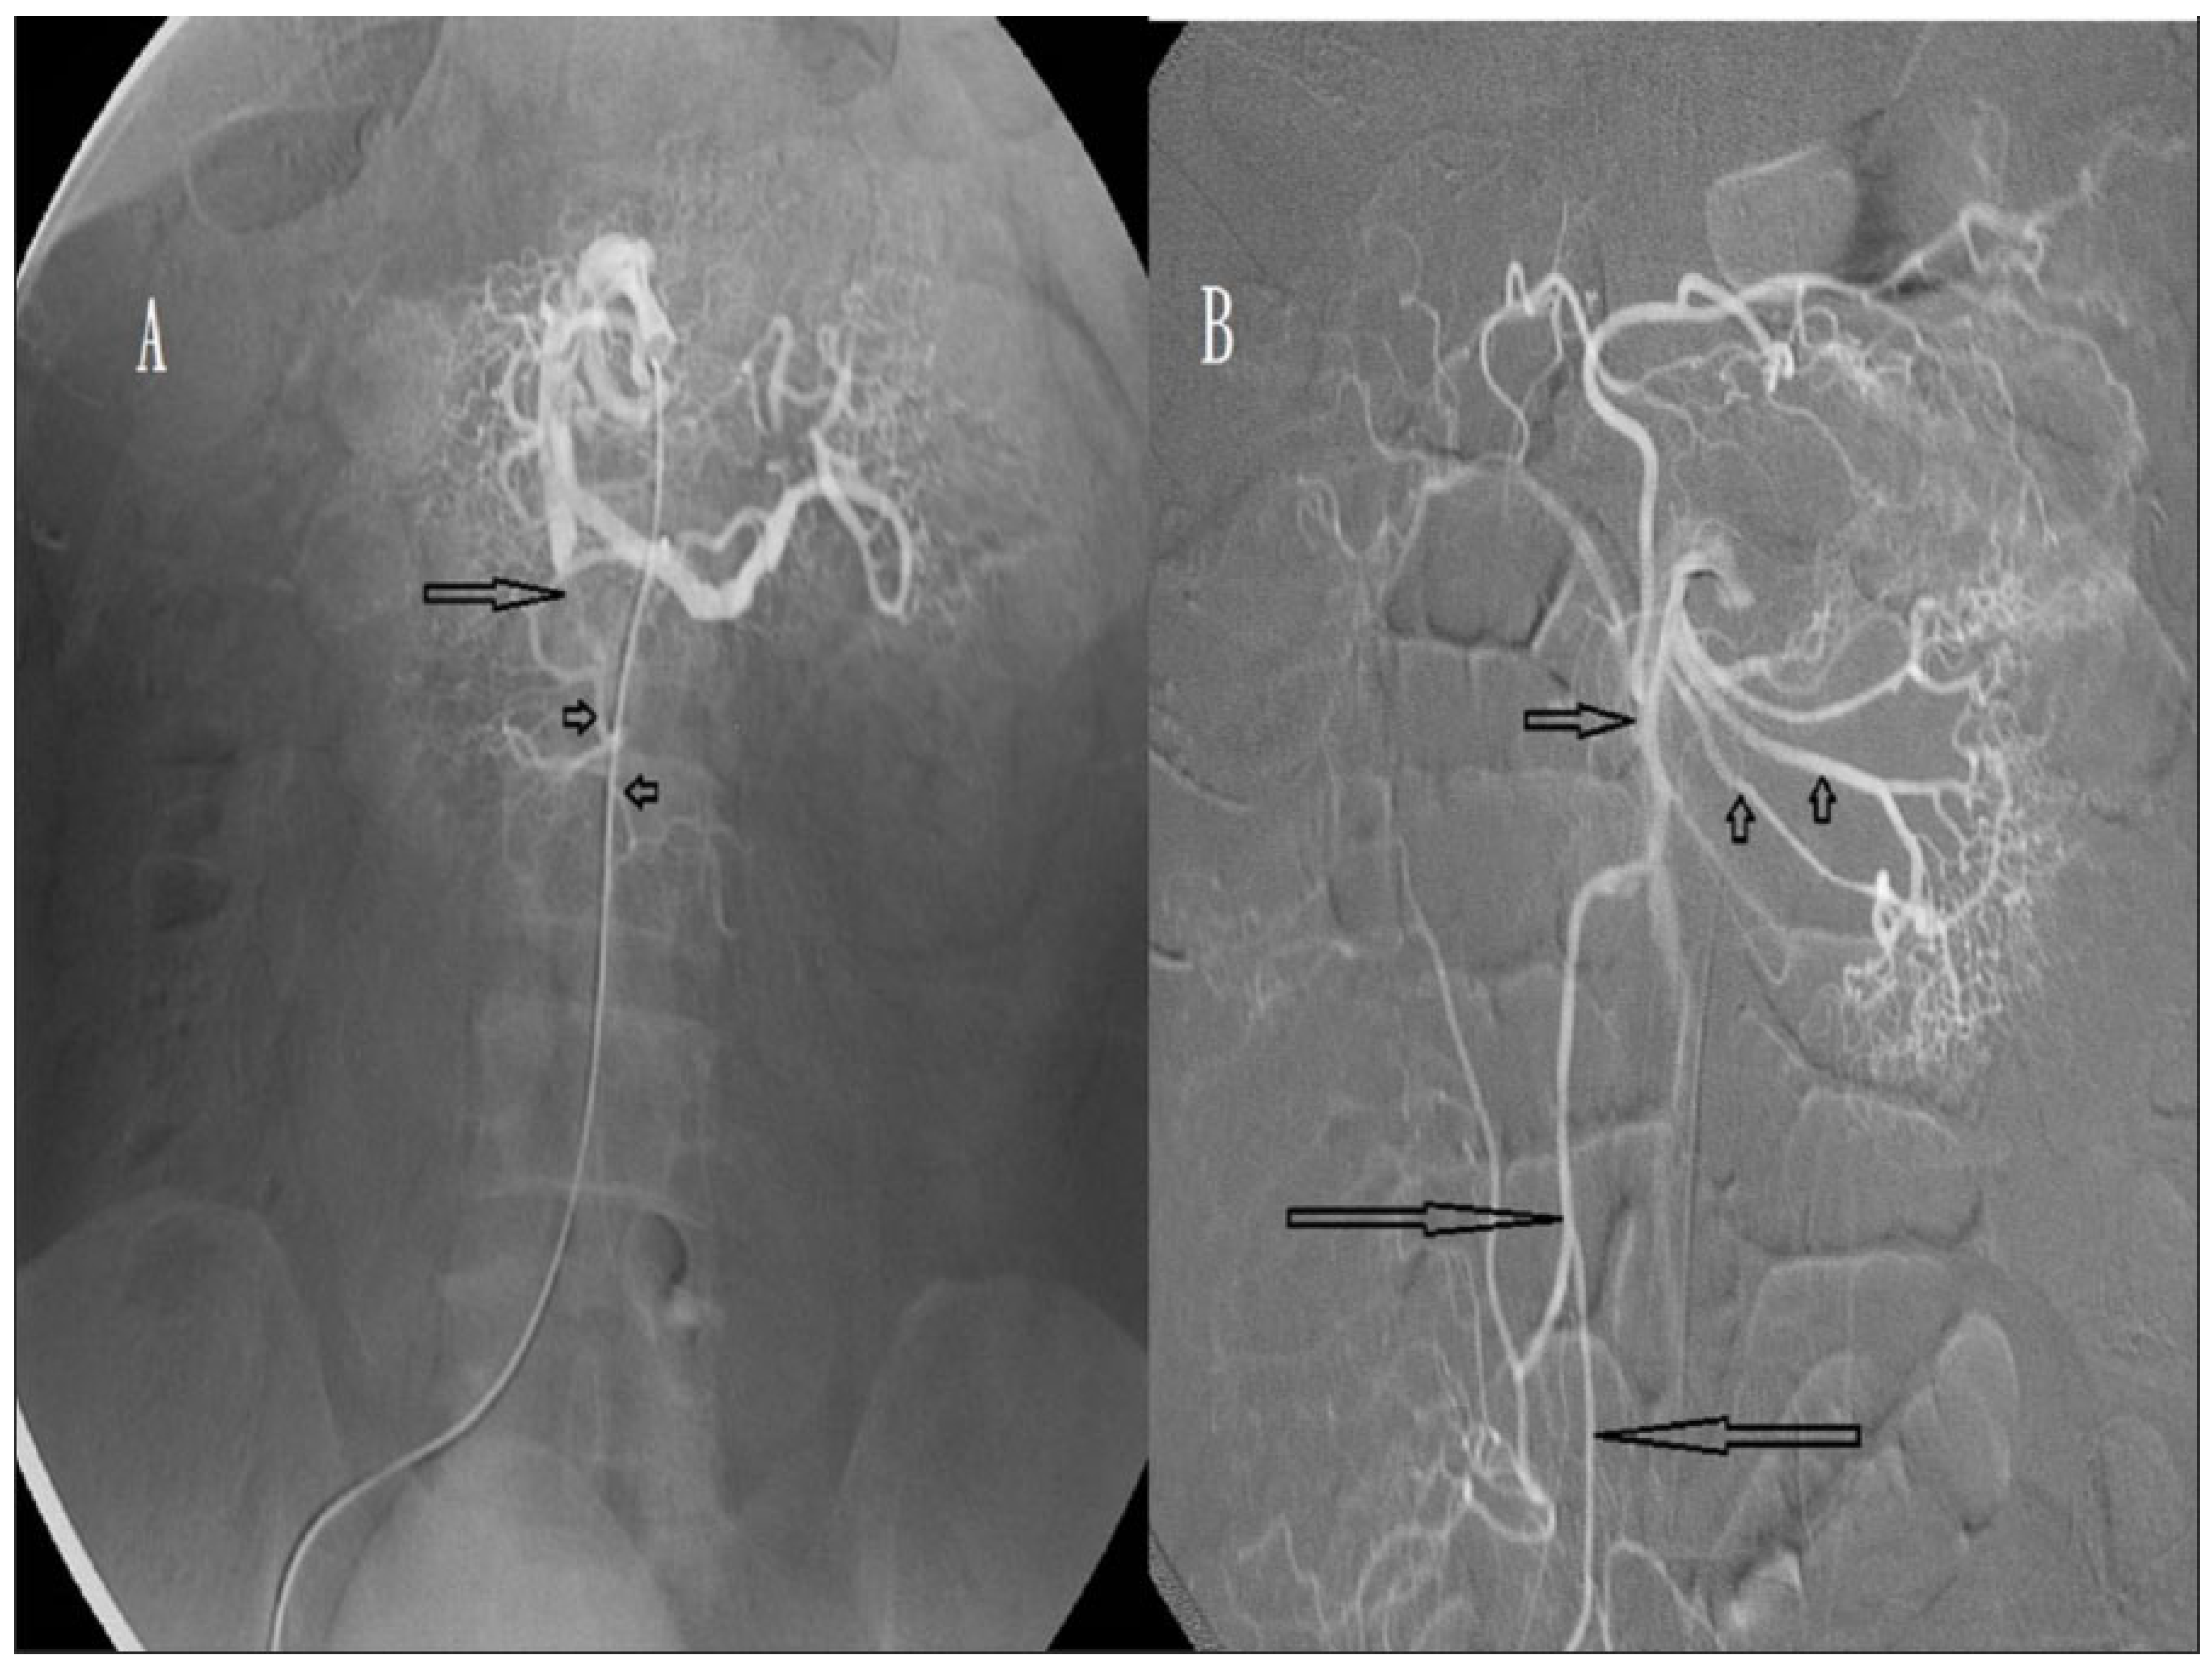

2.4. Procedure